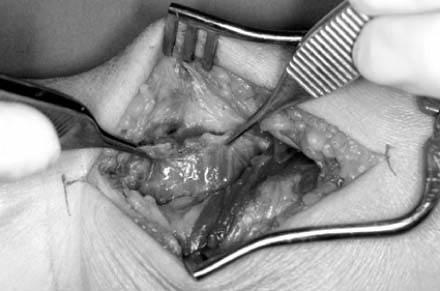

Fig. 9

The pronator quadrates is elevated from the lateral edge of radial orign.

Fig. 9 The pronator quadrates is elevated from the lateral edge of radial orign.